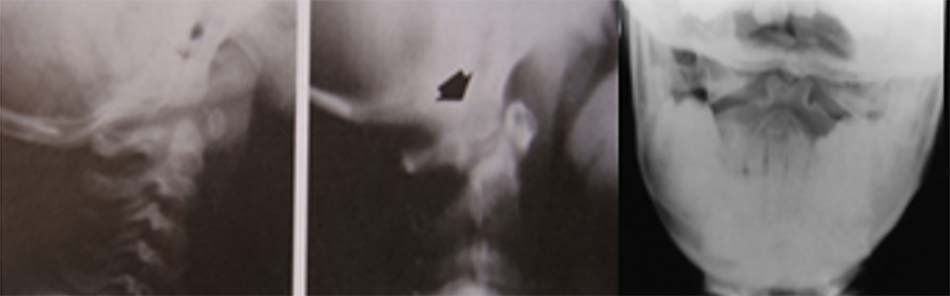

Trong khớp giả mỏm nha, giữa mỏm nha và thân đốt trục có hình ảnh giống một khe khớp nhìn trên phim xquang. Phân biệt hình ảnh khớp giả này với khớp bán động sụn trung tâm thường gặp ở trẻ dưới 5 tuổi. Vì vậy, đối với trẻ dưới 5 tuổi, chẩn đoán khớp giả mỏm nha được xác định bằng sự di lệch của mỏm nha và thân đốt trục trên hình ảnh phim Xquang động.

Ở người lớn, chẩn đoán khớp giả mỏm nha có thể qua Xquang với hình ảnh khe khớp giữa mỏm nha và thân đốt trục. Khe khớp ở khớp giả mỏm nha giữa mảnh tự do và đốt trục thường nằm cao hơn vị trí của diện khớp đội – trục bên và có đường viền nhẵn. Mảnh rời thường có kích thước bằng 1/2 kích thước mỏm nha bình thường, hình tròn hoặc bầu dục, vỏ xương dày.

Khớp giả do chấn thương đường khe khớp hẹp, bất thường và đường gãy thường kéo dài đến thân đốt đội, dưới diện khớp đội – trục bên. Mảnh rời mỏm nha liền với phần trước của đốt đội và di chuyển theo vận động ngửa, gập hoặc nghiêng cổ hai bên.

Đường đo được kẻ dọc theo mặt trên từ bờ sau của đốt trục và đường kẻ dọc theo mặt dưới từ bờ sau của cung trước đốt đội. Khoảng cách lớn hơn 3mm được coi là bệnh lý. Trong nghiên cứu của Fielding và cộng sự, khoảng cách trên là 1 cm và hầu hết bệnh nhân có mất vững trước hoặc sau hoặc đa hướng. Mất vững đa hướng đồng nghĩa với khớp C1-C2 không ổn định.